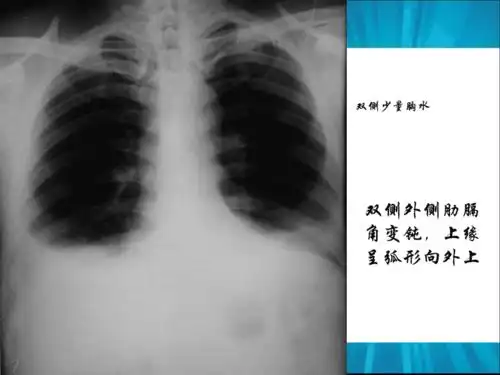

胸腔积液的影像诊断